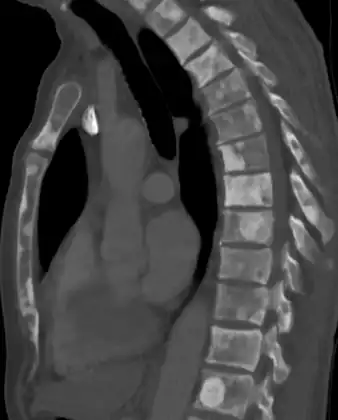

The most important distinction made by any staging system is whether the cancer is confined to the prostate. In the TNM system, clinical T1 and T2 cancers are found only in the prostate, while T3 and T4 cancers have metastasized. Several tests can be used to look for evidence of spread. Medical specialty professional organizations recommend against the use of PET scans, CT scans, or bone scans when a physician stages early prostate cancer with low risk for metastasis.[95] Those tests would be appropriate in cases such as when a CT scan evaluates spread within the pelvis, a bone scan looks for spread to the bones, and endorectal coil magnetic resonance imaging evaluates the prostatic capsule and the seminal vesicles. Bone scans should reveal osteoblastic appearance due to increased bone density in the areas of bone metastasis—the reverse of what is found in many other metastatic cancers.

Sclerosis of the bones of the thoracic spine due to prostate cancer metastases (CT image)